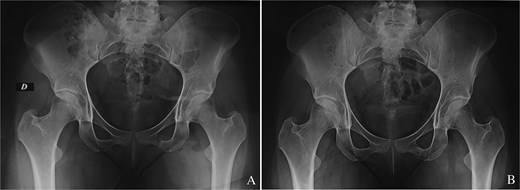

We report the case of a 24-year-old woman with no particular pathological history who complained of buttock pain radiating to the lateral region of the hip and which had been present for 8 months. Most of the pain was nocturnal, resistant to the usual medical analgesic treatment. No spinal or knee symptoms were reported. Clinical examination revealed a well-localized tenderness over the left buttock, corresponding to the ischial region. Mobilization of the hip and knee was painless. Pelvis X-rays showed a millimetric radiolucent area surrounded by an osteosclerosis at the ichiopubic ramus of the left obturator frame (Fig. 1A). The appearance was in favour of an osteoid osteoma. Computed tomography supported the diagnosis (Fig. 1B).

(A) Osteoid osteoma of the left ischiopubic ramus on the anteroposterior view of a pelvic X-ray. (B) Osteoid osteoma of the left ischiopubic ramus on an axial section of the CT scan of the pelvis.

(A) Immediate anteroposterior pelvis X-ray showing the tumour resection. (B) Last follow-up anteroposterior pelvis X-ray showing the absence of tumour recurrence.